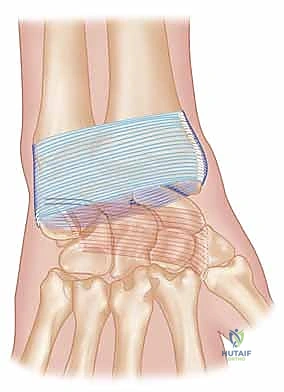

C. Creating the Ulnar Head Tunnel

1. Identifying Drill Site: "Back to the dorsal wrist. We need to create a bone tunnel through the ulnar head." Identify the ulnar head. The drill entry point is typically on the dorsal aspect of the ulnar head, just distal to the articular cartilage.

Image

TECH FIG 2D • A tunnel is drilled in the ulnar head.

1. Drilling the Tunnel: "I'll take a 2.5 mm drill bit, please." Drill a unicortical tunnel through the ulnar head, aiming towards the fovea, or slightly volar and distal to exit on the ulnar styloid or fovea region. The exact trajectory is crucial to mimic the ulnocarpal ligament's course.

TECH FIG 2E • The tendon graft is passed through the ulnar head.

> **Surgical Warning:** Drill under constant fluoroscopic guidance to confirm trajectory and prevent iatrogenic fracture of the ulnar head or damage to the articular surface. Ensure the tunnel is smooth and free of sharp edges that could fray the graft. Use a Kirschner wire to create the pilot hole, then over-drill if necessary.